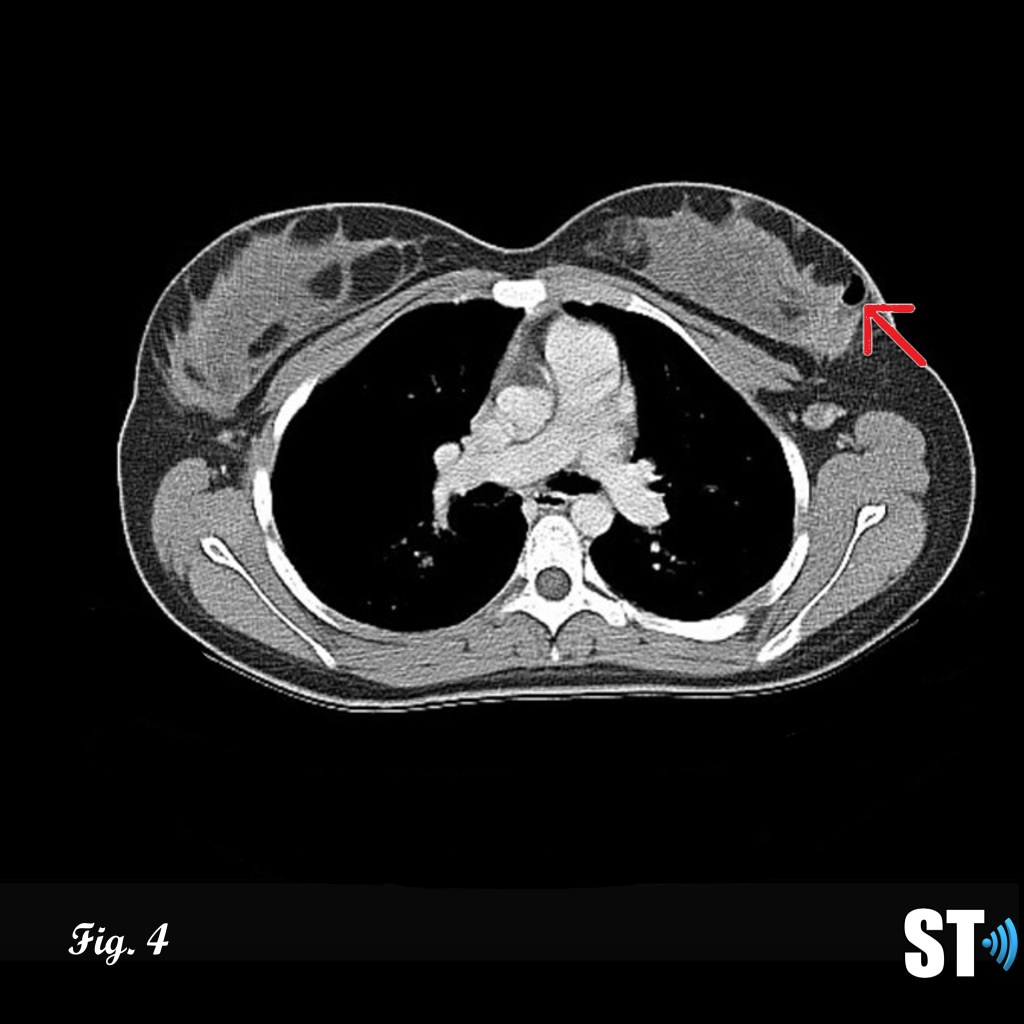

Given the high incidence of recurrence complete surgical resection should be performed. Current guidelines recommend excisional biopsy for benign lesions, while for borderline and malignant lesions the entire mass should be surgically resected with at least 1 cm surgical margins. [10]

Mastectomy – Breast-Conserving vs. Total

In the case of adequate margins via resection and radiation therapy breast-conserving surgery has been found to be as effective as total mastectomy in treating malignant phyllodes. [11] Axillary dissection is typically not recommended due to the low (<1%) involvement of axillary lymph nodes. Mastectomy is not recommended for benign phyllodes except for in cases where the tumor is so large surgical excision will result in cosmetically undesirable results.

Figure 4-5 follow up post lumpectomy with post-surgical changes (air, red arrow) lesion was found to be malignant phyllodes resulting in mastectomy Fig.5 with breast implant in place (white asterisk).